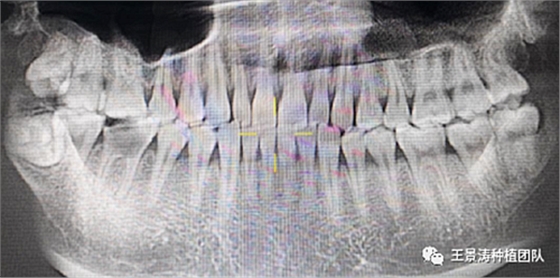

下述病例則是15區(qū)域的即刻種植,15因牙冠折斷于齦下,無法樁核冠修復,則考慮種植修復。但拍攝CBCT后發(fā)現(xiàn)根尖距上頜竇底距離較短?;颊邽槟贻p女性,無全身系統(tǒng)疾病且可利用上頜竇底與根尖皮質(zhì)骨雙側(cè)皮質(zhì)骨固位,且此位置可通過頰側(cè)軟組織減張技術(shù)獲得嚴密封閉牙槽窩。因其根尖距上頜竇距離較低,遂拔除15后行上頜竇內(nèi)提升,埋入式種植,最終修復的完成。

左側(cè)下頜第二磨牙及右側(cè)下頜第一磨牙同時即刻種植病例?;颊吣贻p女性,無系統(tǒng)性疾病。37及46殘冠及殘根,且46劈裂,無法冠修復,必須拔除。37根尖慢性炎癥,大量肉芽組織存在,46根分叉較高,根分叉骨質(zhì)尚可。CBCT示:根尖骨質(zhì)至下牙槽神經(jīng)管距離可滿足種植體的初期穩(wěn)定性,遂考慮即刻種植,并在種植體周邊填入骨粉并覆蓋骨膜,雙側(cè)的種植體初期穩(wěn)定性相差無幾,但考慮到37根尖慢性炎癥較大,遂給予埋入式種植。